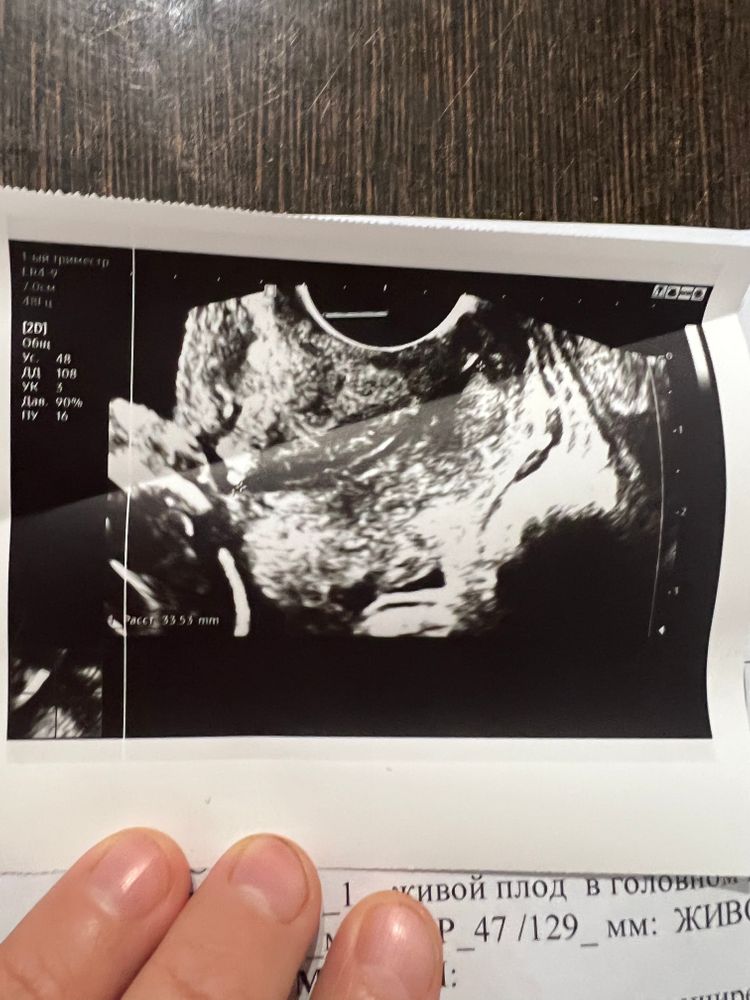

Беременность 15 недель после эко. Сегодня сделала узи и появилось много вопросов.

5. На скрининге в 11,4 шейка была 48 мм, сегодня же 33 мм. Как так быстро она уменьшилась?

На скрининге все было хорошо , а сейчас много чего не понятного для меня. Узи прилагаю